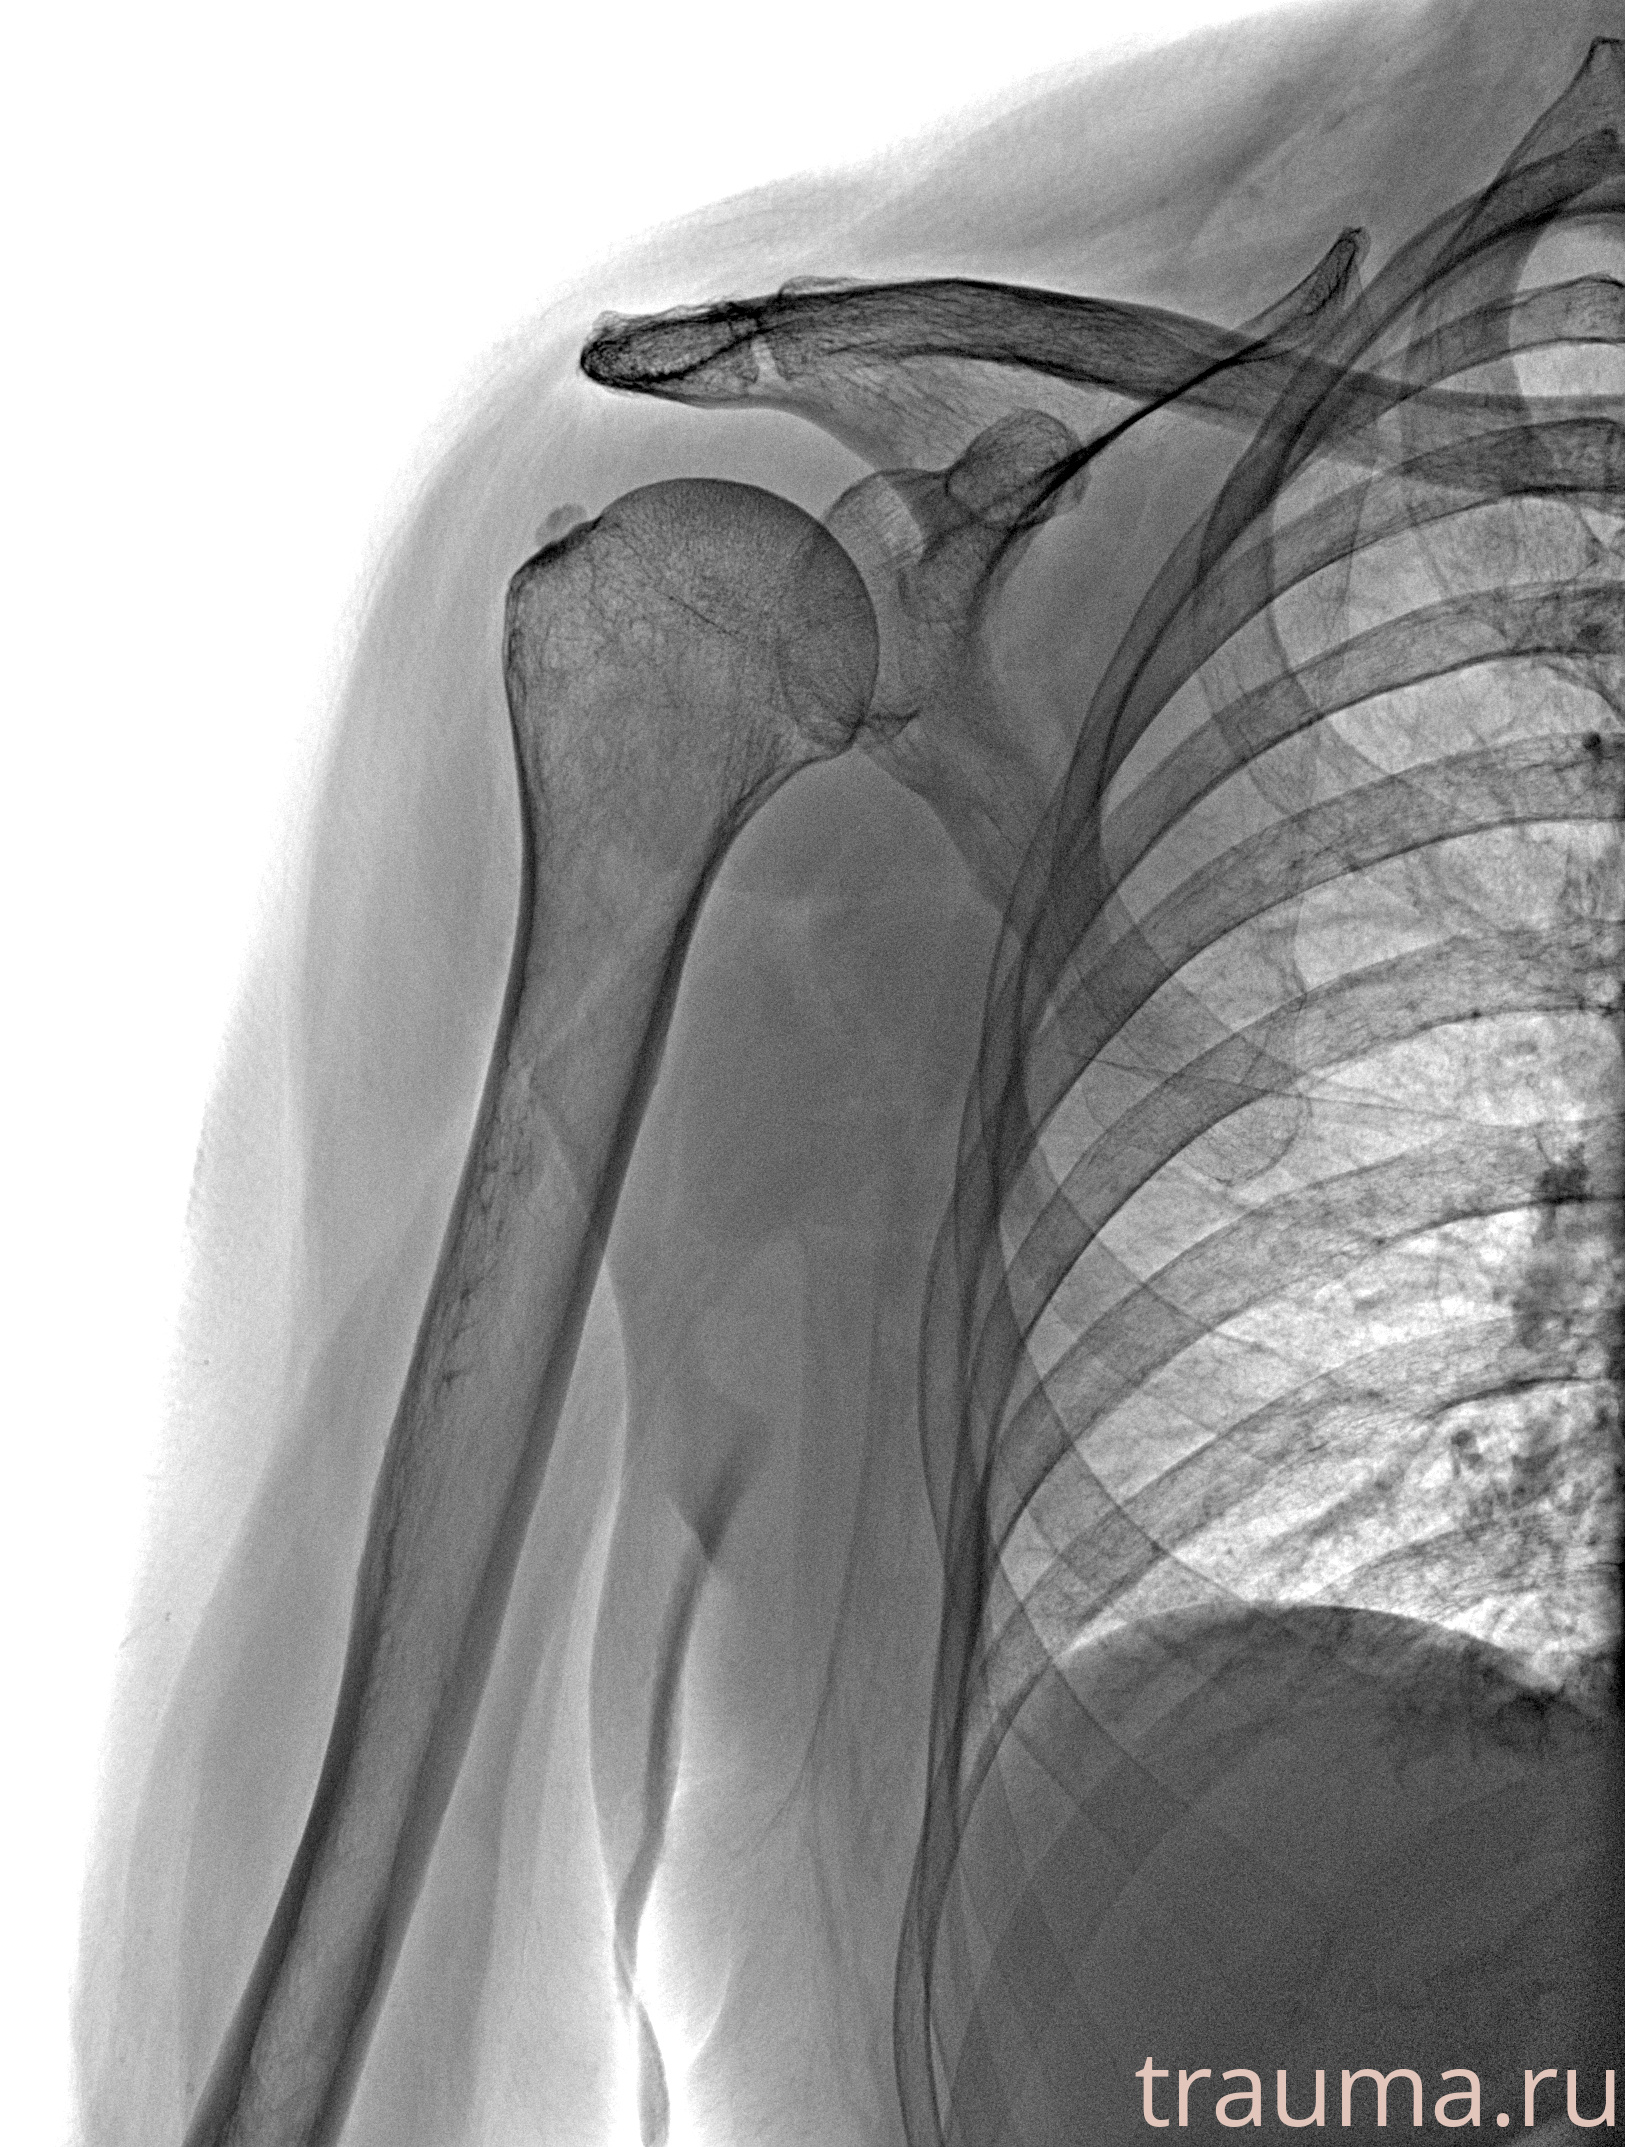

Рентген на дому: по вашему адресу приезжает врач-рентгенолог, травматолог-ортопед с мобильным рентгеновским аппаратом, проводит диагностику травмы или заболевания, делает необходимые рентгенограммы, дает рекомендации по дальнейшему лечению. Получить качественные снимки в домашних условиях возможно благодаря уникальной методике, разработанной МосРентген Центром для института  Склифосовского